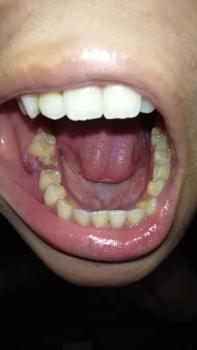

Mandibular Arch (Lower Jaw):

Moderate to Severe Crowding: The lower anterior (front) teeth are visibly rotated and overlapping, indicating significant space deficiency.

Gingival Status: While not the primary focus, the crowding makes effective brushing and flossing difficult, which can lead to increased plaque retention, gingivitis, and potential periodontal issues in the future.